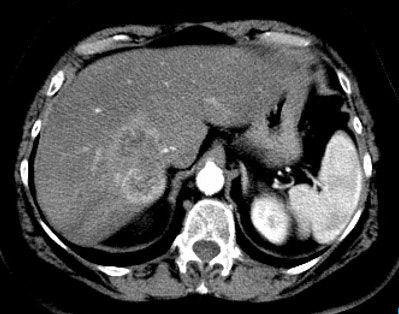

Gastrointestinal stromal tumor: The patient below had a large gastric GIST tumor (white arrow). FDG PET imaging demonstrated markedly increased, heterogeneous tracer uptake by the mass (black arrows). There was no evidence of metastatic disease. |

|